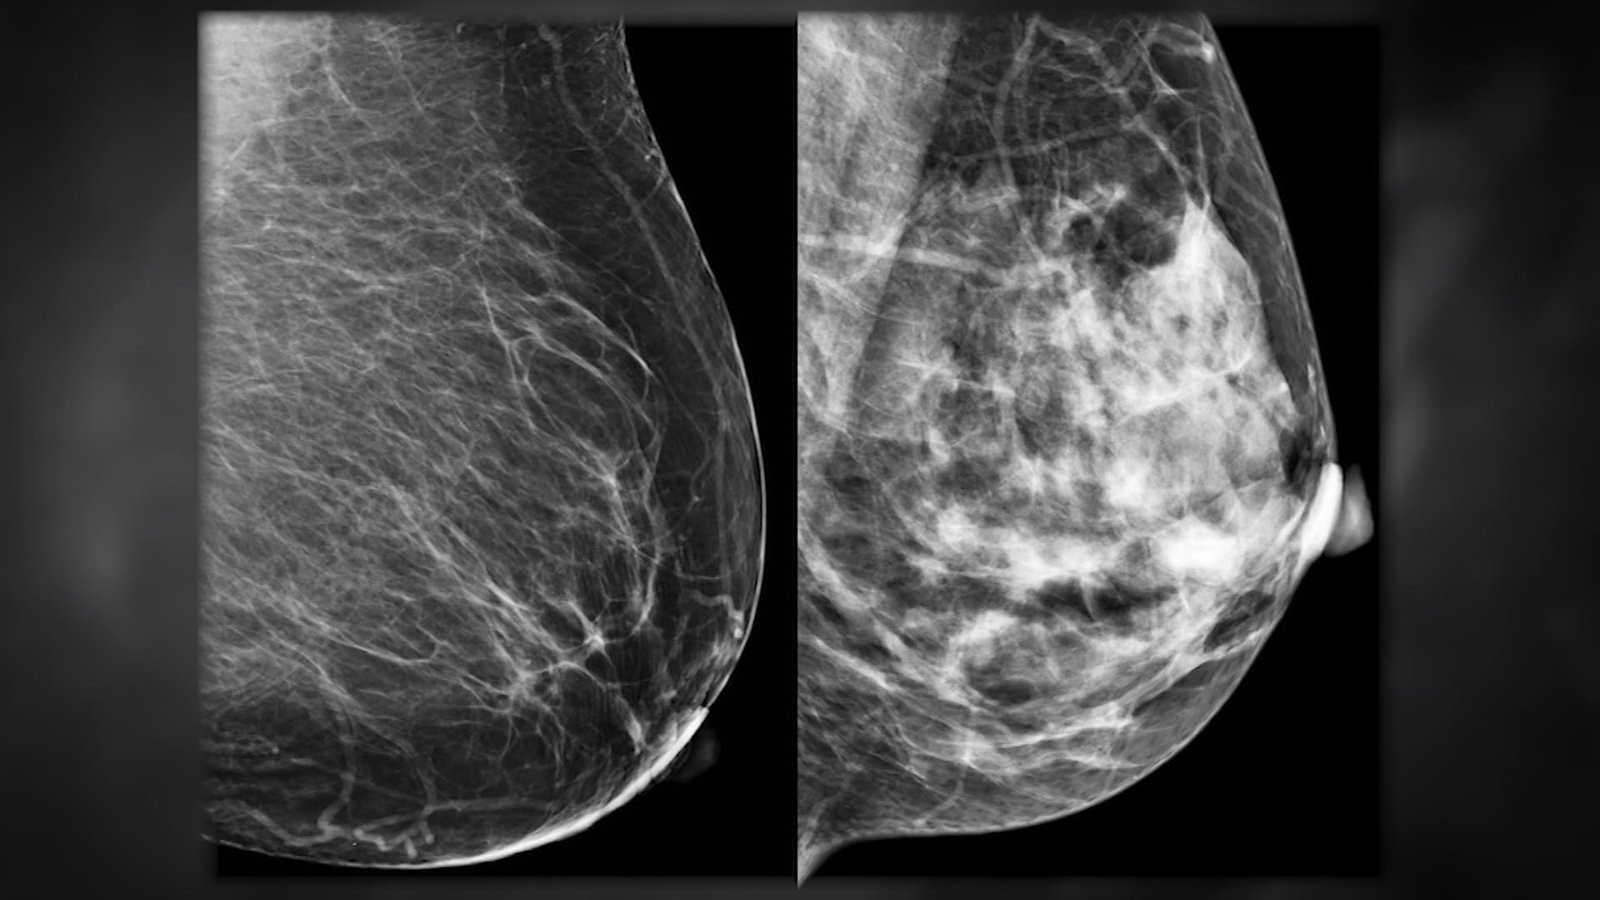

ازيح الستار عن تقنية جديدة تعمل بالذكاء الاصطناعي تقوم بتحليل صور الماموغرام، إلى جانب عمر المريضة، لتقدير احتمال إصابتها بسرطان الثدي خلال الخمس سنوات القادمة. ويعمل هذا النظام مع الصور الثنائية الأبعاد التقليدية وصور التصوير المقطعي ثلاثي الأبعاد للثدي، ما يجعله قابلًا للتطبيق على أنواع الفحص المعتمدة في العيادات والمستشفيات. كما يوفّر النظام نسبة مئوية دقيقة تمثل درجة خطر الإصابة، ما يمكّن الأطباء من مقارنة مستوى الخطر لدى المريضة بالمعدل الوطني العام.

أظهرت النتائج أن هذه التقنية القائمة على الذكاء الاصطناعي تحقق دقة تصل إلى أكثر من ضعف دقة الطرق التقليدية التي تعتمد فقط على استبيانات لعوامل الخطر مثل العمر والوراثة والتاريخ العائلي. وقد تم تدريب الخوارزمية على صور لمئات الآلاف من الحالات، ما مكّنها من التعرّف على مؤشرات دقيقة للغاية للسرطان، لا يمكن ملاحظتها بالعين المجردة. وبما أن البنية التحتية لفحص الماموغرام موجودة بالفعل في معظم المستشفيات، فمن السهل دمج هذه التقنية في الإجراءات الصحية المعتمدة دون الحاجة لاستثمارات جديدة.

الكشف المبكر عن سرطان الثدي يشكّل فارقًا كبيرًا في فرص النجاة، إذ أن أغلب الحالات التي يتم اكتشافها في مراحل مبكرة يمكن علاجها بنجاح بنسبة تصل إلى 99%. في المقابل، تشكّل الحالات التي تُكتشف في مراحل متأخرة نسبة كبيرة من إجمالي الإصابات، وهو ما يؤدي إلى مضاعفات صحية وعلاجية أكبر. لذا فإن التقدير المبكر لخطر الإصابة يعطي فرصة لتدخّل وقائي، سواء عبر الفحوصات الإضافية أو عبر استراتيجيات طبية تقلل من احتمالية تطور المرض في المستقبل.